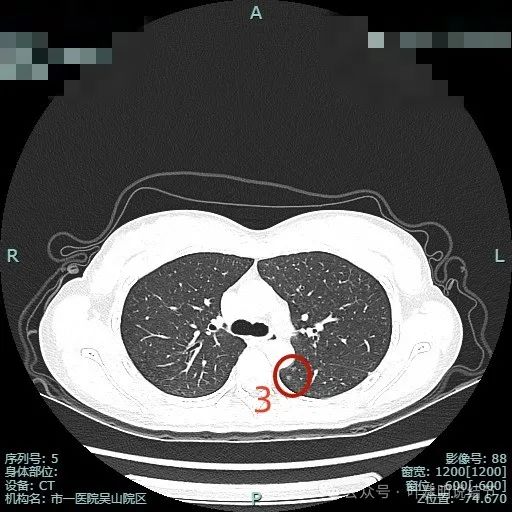

病灶3:左下叶淡磨玻璃结节,整体轮廓较清,考虑肺泡上皮增生或不典型增生可能。似乎是两处,但靠前侧的不太确切。